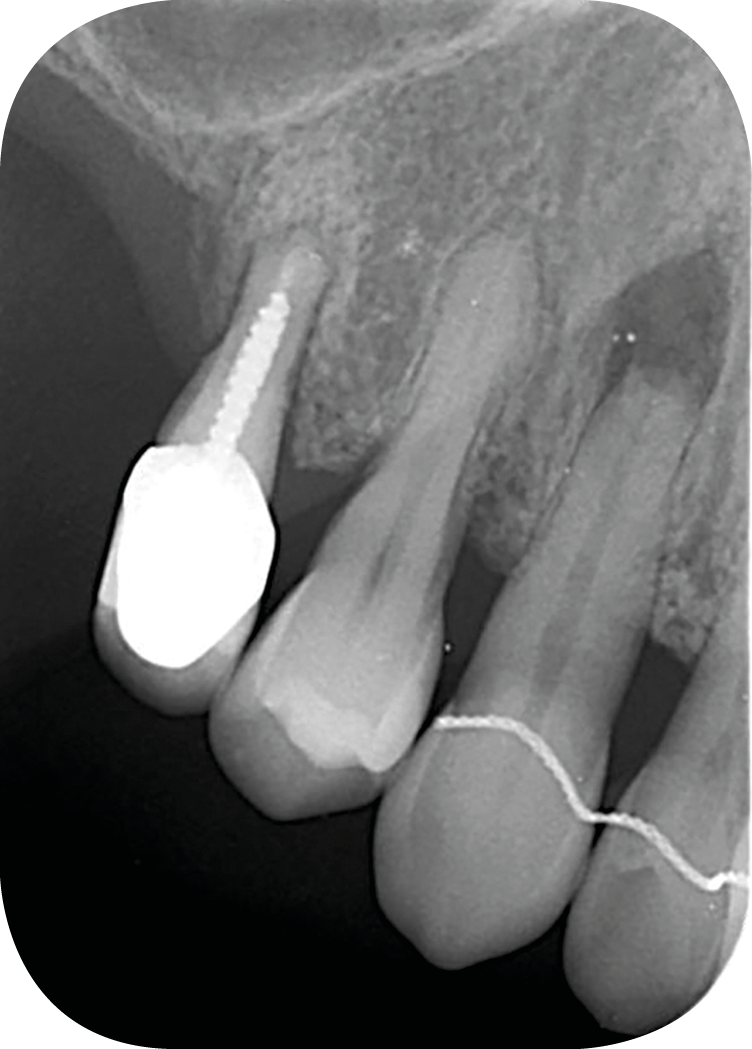

– les soins conservateurs et endodontiques [5] (fig. 4 et 5).

Les soins conservateurs et endodontiques sont majoritairement responsables des dyschromies des dents dépulpées. Nous allons développer ce point afin de mieux comprendre les paramètres régissant les colorations iatrogènes pour mieux les éviter et, si besoin, les corriger.

Ainsi, les ciments d’obturation canalaire sont la cause principale des dyschromies de la dent dépulpée [6]. Les modifications de couleur peuvent apparaître après une semaine seulement, lorsqu’il s’agit de ciments oxyde de zinc/eugénol (ZoE) [7, 8] ou à un mois post-traitement dans le cas de certaines biocéramiques [6].

Parmi les agents responsables de cette dyschromie, on peut citer l’eugénol, contenu dans les ciments ZoE et l’oxyde de bismuth, utilisé comme radio-opacifiant dans certaines biocéramiques, et principalement le MTATM [9]. L’oxyde de bismuth, quelle que soit sa concentration, même modérée dans le cas du MTA WhiteTM, provoque une coloration iatrogène de la dent en quelques semaines seulement [10] (fig. 6) [10]. Afin d’éviter ce type de dyschromies en secteur esthétique, il s’agit donc de privilégier dans notre pratique des biocéramiques qui contiennent un autre radio-opacifiant tel que l’oxyde de zirconium qui, lui, ne va pas créer de coloration iatrogène (BiodentineTM, TotallfillTM ou le BioRootTM) [11].